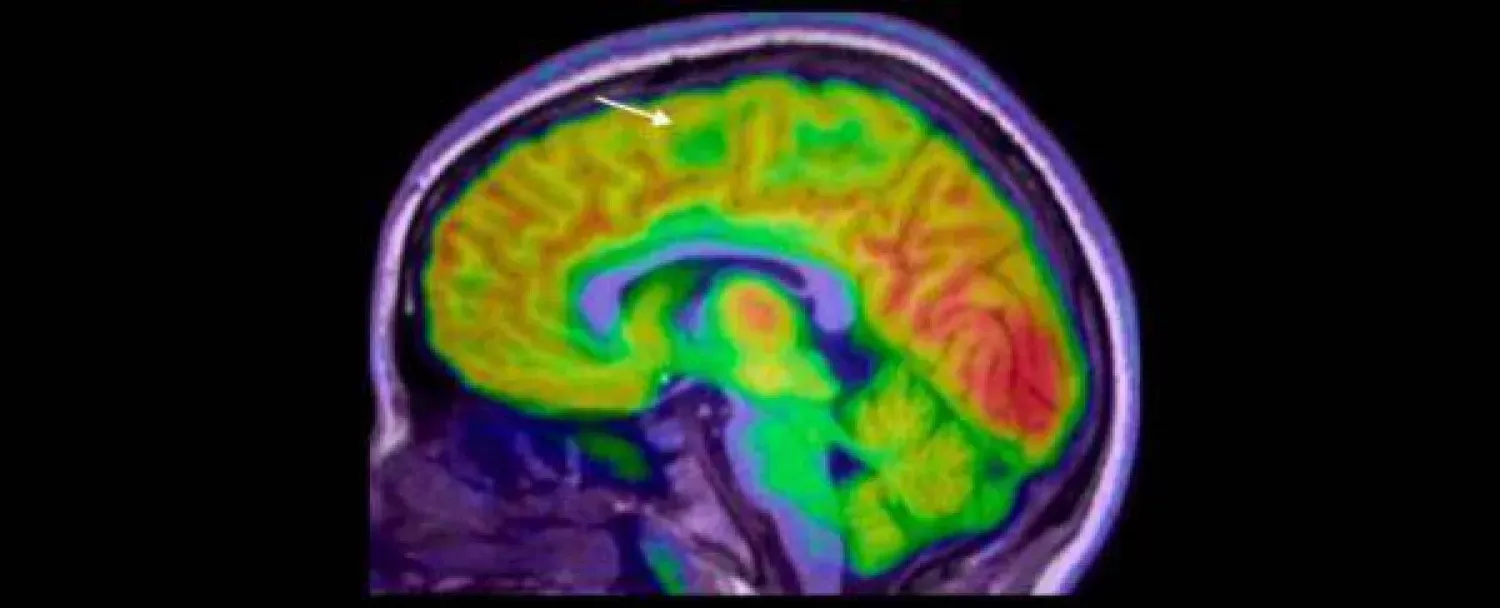

نجح فريق بحثي من «معهد مردوخ لبحوث الأطفال» (Murdoch Children's Research)، والمستشفى الملكي للأطفال، بملبورن في أستراليا، في تطوير جهاز لتشخيص الصرع بالذكاء، يستطيع رصد وجود خلل في أنسجة القشرة المخية، لا يمكن رصده من خلال فحص الأشعة العادي.

وأوضحت الدراسة التي نُشرت في نهاية شهر سبتمبر من العام الحالي، في مجلة «الصرع» (Epilepsia)، أن الجهاز الجديد قادر على التشخيص بدقة لأي خلل صغير في أنسجة القشرة المخية، ما يؤدي إلى تدخلات جراحية أسرع لعلاج حالات الصرع العنيفة، ومن ثَمَّ تقليل تكرار النوبات، وتحسين نتائج النمو على المدى الطويل.

من المعروف أن الجراحات الحرجة مثل التي يتم إجراؤها في المخ، تعتمد بشكل أساسي على دقة التشخيص من خلال التصوير المتقدم للأنسجة؛ حيث يُمكن لجرَّاح الأعصاب إجراء جراحة أكثر أماناً، لتجنب الأوعية الدموية المهمة، ومناطق المخ التي تتحكم في الكلام والتفكير والحركة، وأيضاً لتجنب استئصال أي أنسجة سليمة عن طريق الخطأ.

قام الباحثون باستخدام التصوير بالرنين المغناطيسي لتدريب الجهاز الجديد، وبعد ذلك قاموا بتقسيم الأطفال إلى مجموعتين للتدريب، كما استُخدمت مجموعة منفصلة من فحوصات البالغين للتحقق الإضافي من أداء الجهاز.

ومن خلال فحص أشعة الرنين المغناطيسي، تمكن الجهاز الجديد من تشخيص معظم الحالات بنسبة نجاح بلغت 94 في المائة ،ومن بين 17 طفلاً في المجموعة التجريبية، خضع 12 منهم لعملية جراحية، وتعافى 11 منهم الآن من النوبات.

أكد الباحثون أن اكتشاف وجود الخلل في نسيج القشرة المخية من خلال فحوصات الرنين المغناطيسي الروتينية، يُعد أمراً بالغ الصعوبة؛ حيث يتم التعرف على أقل من نصفها فقط في أول فحص للطفل، ما يؤخر التشخيص، ومن ثَمَّ يحرم الطفل من فرصة إجراء الجراحة في وقت مبكر، وكلما طالت مدة معاناة الطفل من النوبات شديدة الحدة، زاد احتمال إصابته بصعوبات التعلم، بما في ذلك الإعاقة الذهنية.